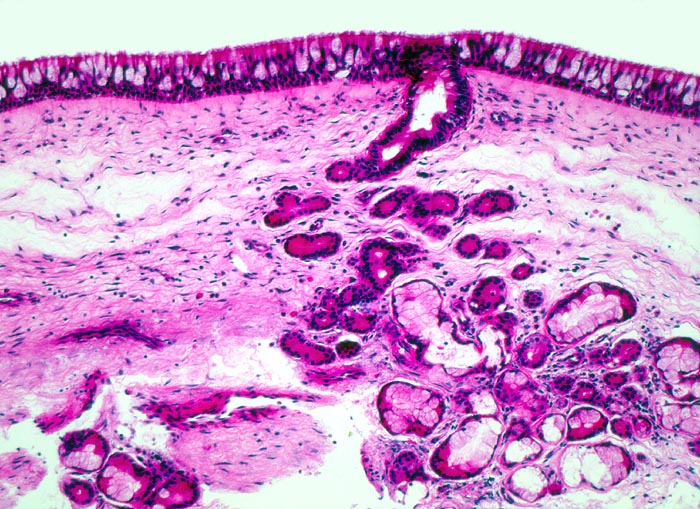

PathoPic – image database / PathoPic ID 4378 - respiratorisches Epithel: Nasennebenhöhlenschleimhaut

respiratorisches Epithel: Nasennebenhöhlenschleimhaut

Sinus ethmoidalis

Relativ dichtes weitgehend entzündungsfreies subepitheliales Stroma mit seromukösen Schleimdrüsen. Die Mukosa besteht aus einem mehrreihigen Epithel mit Flimmerzellen und Becherzellen.